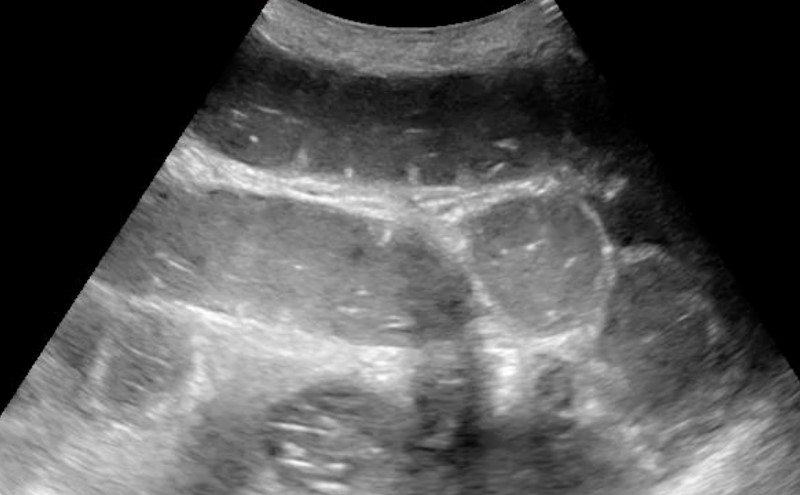

- The small bowel can be identified by visualizing the plicae circularis. Bowel wall edema in SBO can accentuate these structures, creating the “piano key sign” or “keyboard sign.” Of note, the analogous haustra of the large intestine are sparser and spaced much further apart.